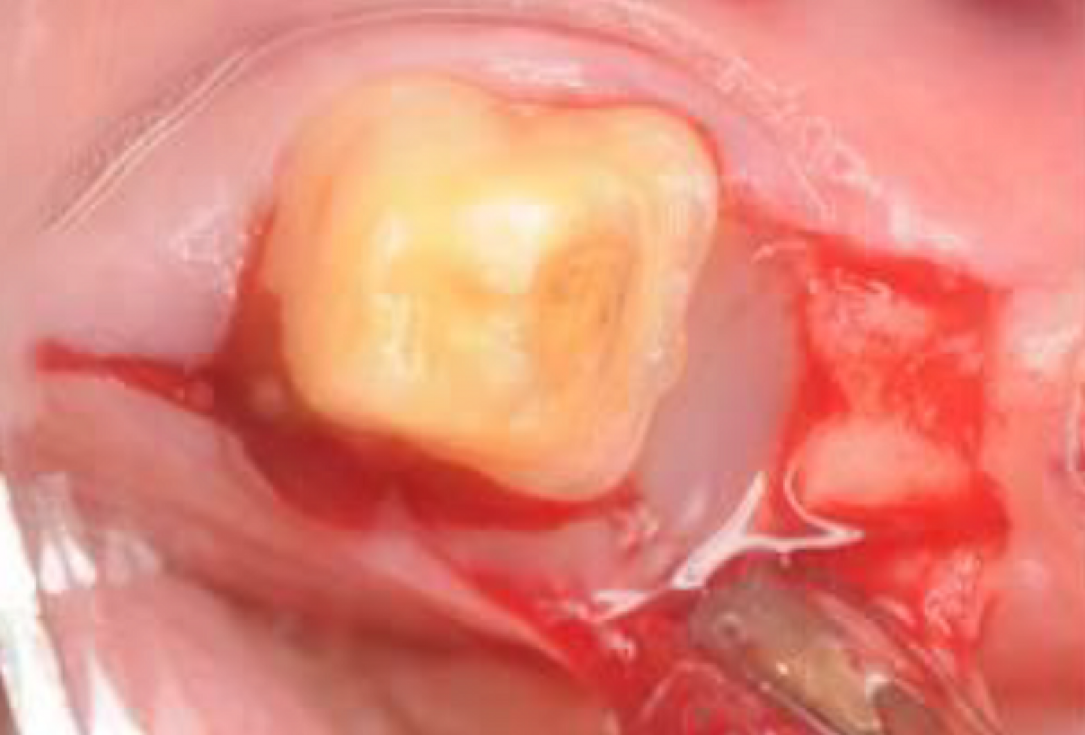

03/06 - Straumann® Emdogain® applied to the defect area.Intrabony defect treated using Straumann® Emdogain®, cerabone® and Jason® membrane - Dr. D. B. Hangyási